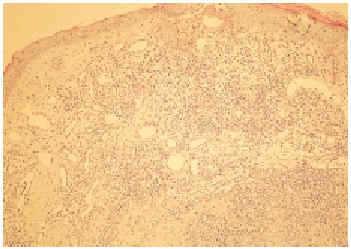

En el estudio histológico se apreció, bajo una epidermis suprayacente adelgazada y ulcerada en algún punto, una proliferación vascular mal definida en la dermis reticular superficial y media acompañada de un denso infiltrado inflamatorio (fig. 2). Esta proliferación estaba constituida por vasos con luces de diámetro variable, de pared fina en la dermis superficial y gruesa en la dermis media. Los endotelios vasculares se componían de células prominentes, con amplios citoplasmas eosinófilos y núcleos vesiculosos, pero no se apreciaban ni pleomorfismo ni mitosis. En algunas zonas de la dermis media la proliferación vascular era muy densa, a modo de cordones celulares de aspecto epitelioide con luces vasculares pequeñas y escasas. El infiltrado inflamatorio que rodeaba a estos vasos se componía predominantemente de linfocitos y de un gran número de eosinófilos (fig. 3).

Fig. 2.--Proliferación vascular en la dermis reticular superficial y media acompañada de un denso infiltrado inflamatorio, con una epidermis suprayacente adelgazada y ulcerada en algún punto.